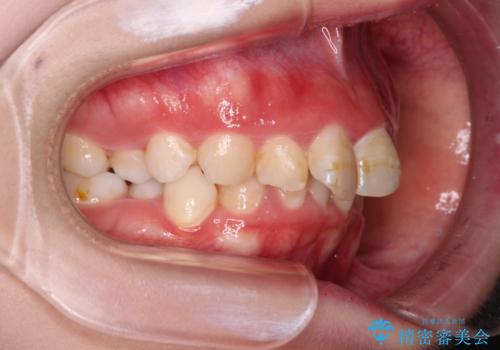

極端な出っ歯という訳ではありませんでしたが、叢生が強かったため、上下左右の第一小臼歯4本を抜歯し、少しでも口元の突出感を改善できるよう治療計画を立案しました。

下顎前歯が隠れるほどのディープバイトであり、それによる顎の負担も大きかったため、ディープバイトもしっかりと改善できるよう、表側のワイヤー装置にて矯正治療を行うこととしました。

骨格的に下顎骨が左側にシフトしていたため、上下正中の位置や左側臼歯部の咬合を理想的に仕上げることはできませんでしたが、非常に綺麗な口元を達成することができました。